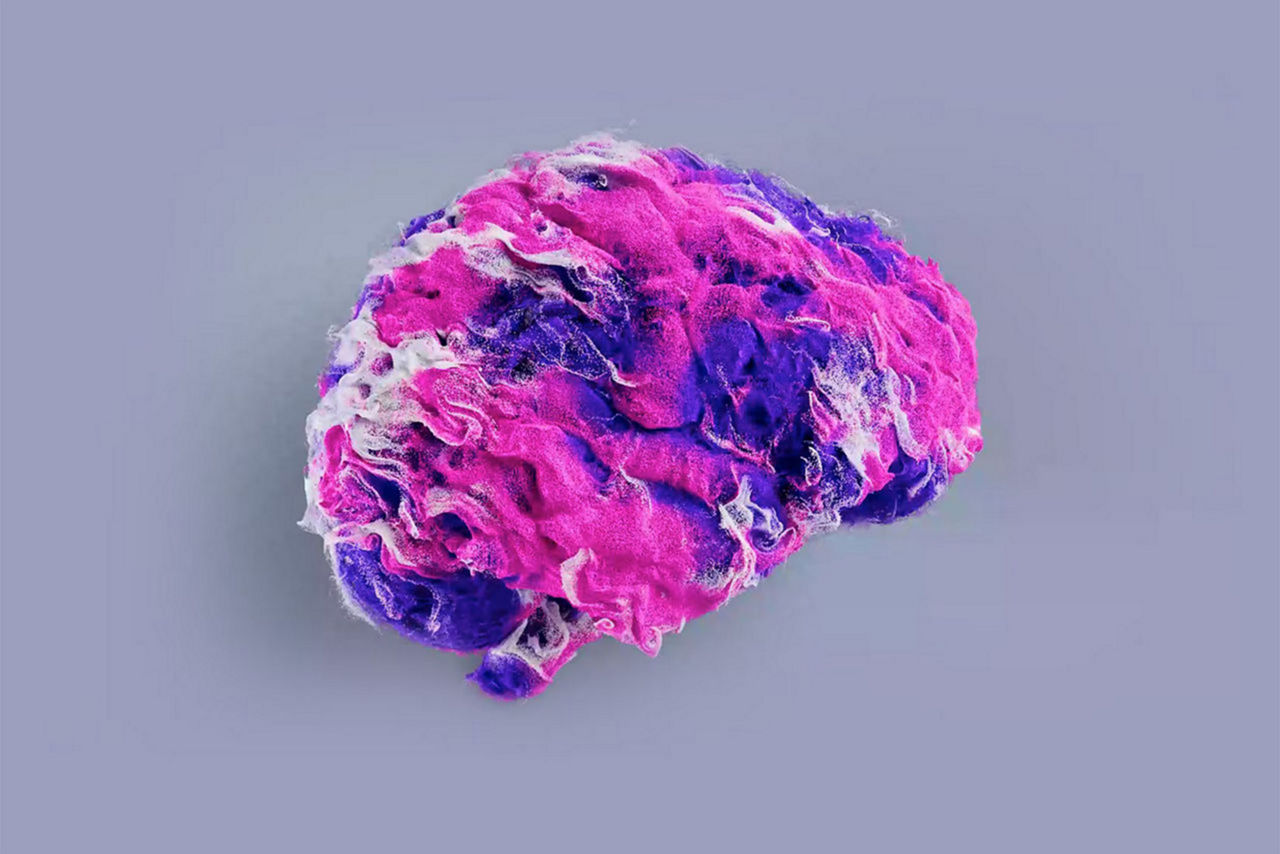

A premium head-only scanner for neurological discovery

A strong and fully usable 300m T/m / 750 T/m/s gradient power

Oscillating Diffusion Encoding (ODEN) for next-level diagnostic imaging.

Industry-leading AI to drive your neurological breakthroughs

AIR™ Recon DL has revolutionized MRI with its deep-learning-based image reconstruction algorithm. It enables democratization of imaging excellence across the portfolio and for every anatomy. From image noise to ringing, AIR™ Recon DL helps prevent artifacts from ever being introduced to your images. The result is accurate MRI images so clear and so sharp, you can be sure there is nothing in between you and what you need to see.

AIR™ Recon DL transforms 3T MRI as never before by reducing scan times up to 50% and increasing the resolution to sub-millimeter levels. AIR™ Recon DL gives you the freedom to explore the boundaries of 3T imaging.